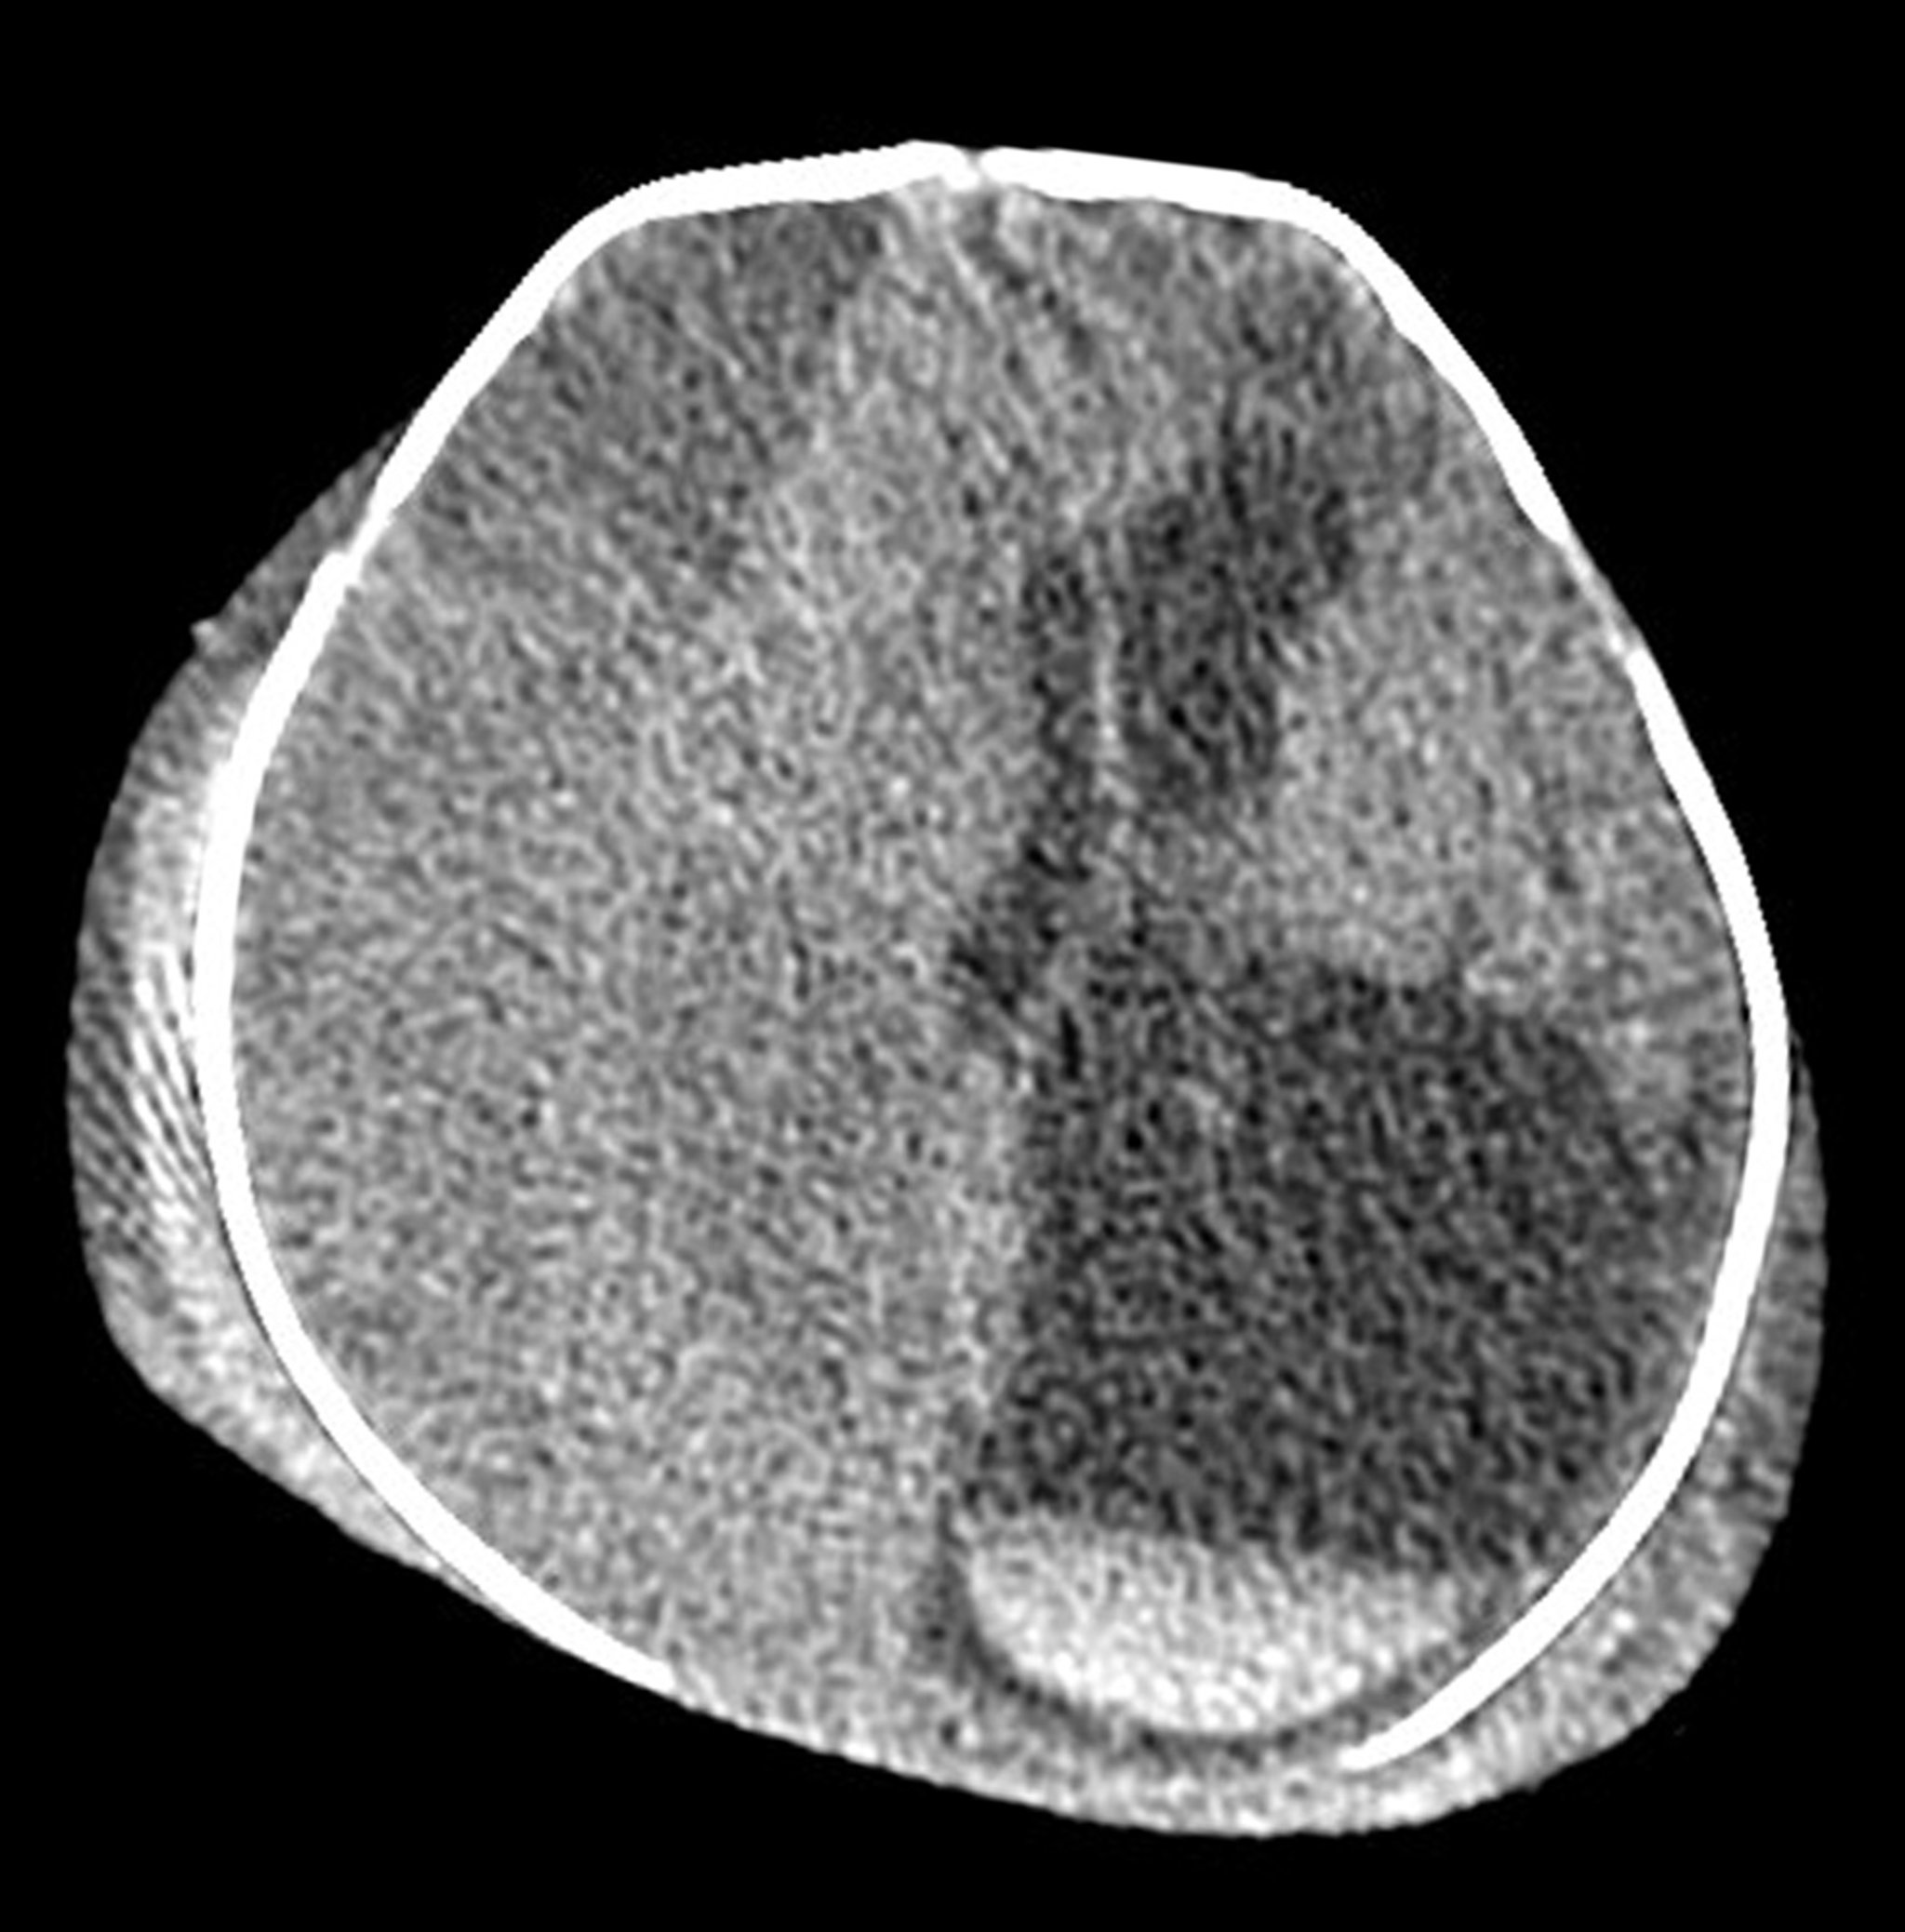

Lésions de naissance extensives chez un nouveau-né (TDM)

Cette TDM axiale (en coupe transversale) de la tête d'un nouveau-né montre des lésions extracrâniennes et intracrâniennes étendues secondaires à des blessures graves liées à la naissance. Il existe une formation bilatérale (gonflement/hématome) dans le cuir chevelu. Il existe un très grand hématome sous-dural isodense (subaigu) le long de l'hémisphère cérébral droit, qui provoque une hernie cérébrale qui passe la ligne médiane. L'hématome entraîne une augmentation de volume du ventricule latéral gauche. Des couches aiguës de sang dans le bas du ventricule latéral gauche (matériau blanc avec une ligne droite) sont visibles dans la partie inférieure droite de l'image.